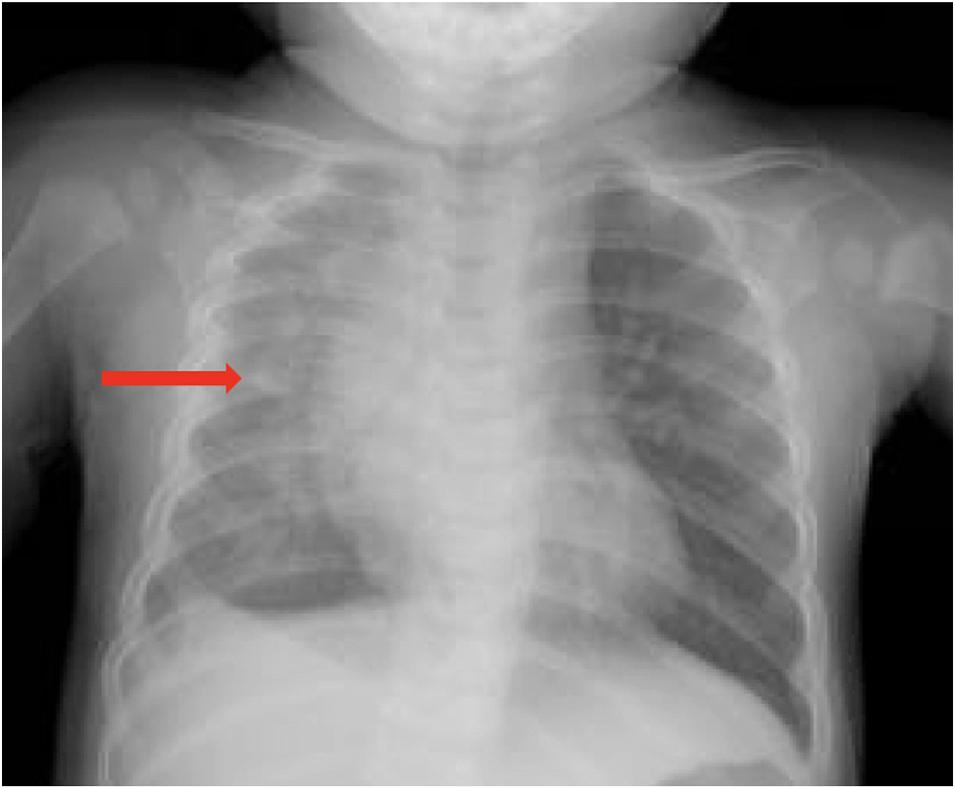

sustainedabitetohisleftthumbfromapetdog.Thedogwas fullyvaccinatedandhadnotbeendemonstratingabnormal behaviorsleadinguptotheincident.Onarrivalthepatient appearedacutelyill.Vitalssignswerenotableforaheartrate of108beatsperminute,bloodpressureof78/43millimeters ofmercury,tachypneaatarateof38breathsperminute,and atemperatureof36.3° Celsius.Examinationoftheulnar aspectoftheleftthumbrevealedtwofaint,punctatebite marksthatlaterbecameduskyandlocallynecrotic (Image1).Darkpurple,non-blanchingmaculeswereseenin allextremitiesconsistentwithpurpurafulminansandhighly suggestiveof Capnocytophaga septicemia(Image2).

Image1. Lefthandwithpurpuraandlocalnecrosis(arrows)as wellaspetechiae(asterisk).

Image2. Pupurafulminans(arrows)oftheleftandrightlower extremities,respectively.